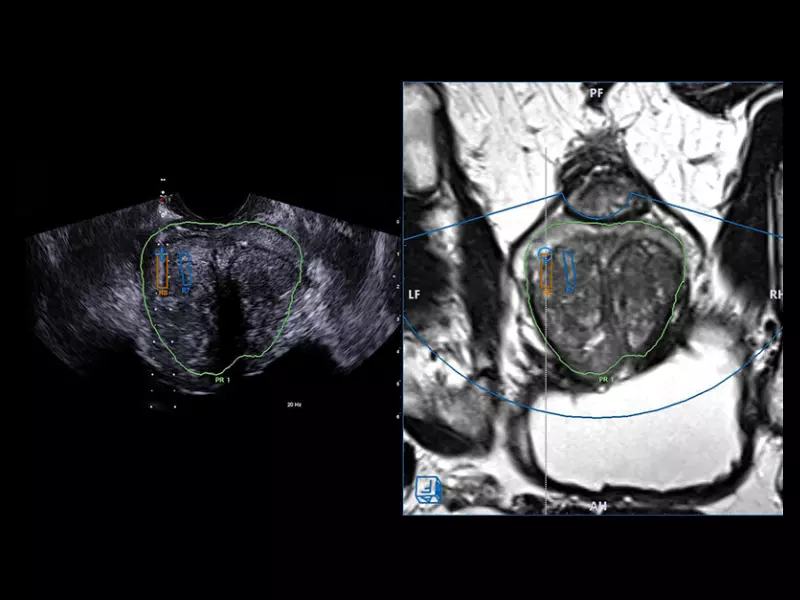

MyLab™X90 - UroFusion Automatic segmentation of the prostate MRI/US, followed by autoregistration of both modalities for targeted biopsies

MyLab™X90 - UroFusion Automatic segmentation of the prostate MRI/US, followed by autoregistration of both modalities for targeted biopsies